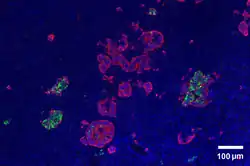

Pancreatic Islets